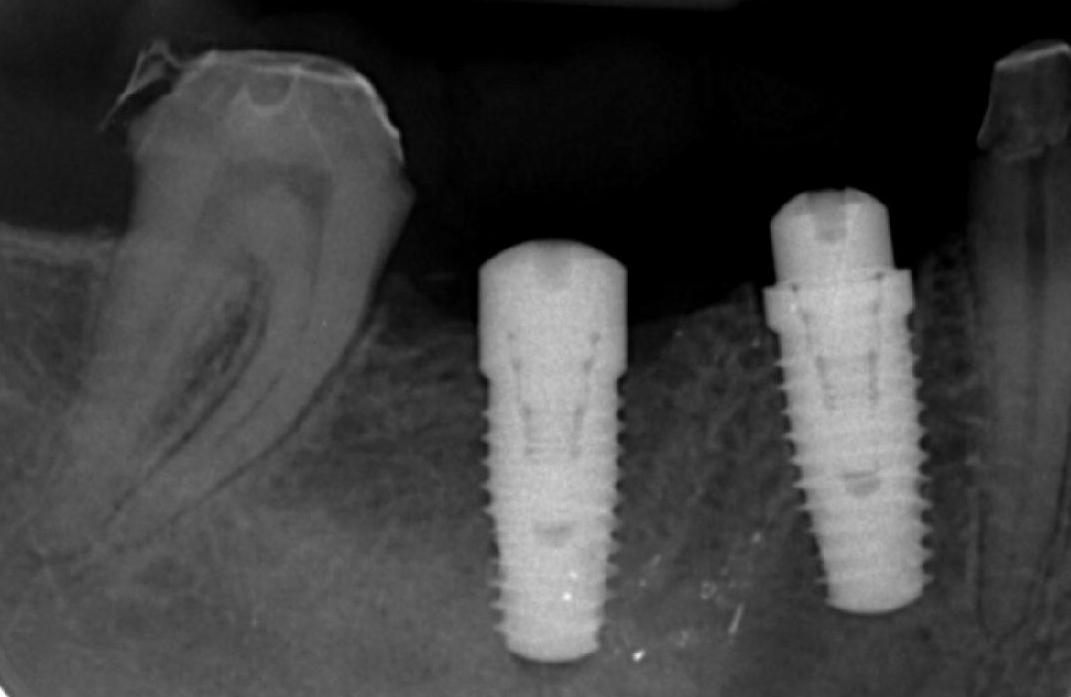

Afterwards an x-ray will be needed and sometimes a 3D CT scan is also necessary to determine the condition of the jawbone. CT scans can show much more than a dental x-ray, and the picture can be laterally cut into slices. Before starting the procedure the patients are given an opportunity to learn absolutely anything and everything they need to know about what the procedure will entail. Any questions should be welcomed by your dental implantologist. Including the opportunities and potential risks as well.

image: 1.